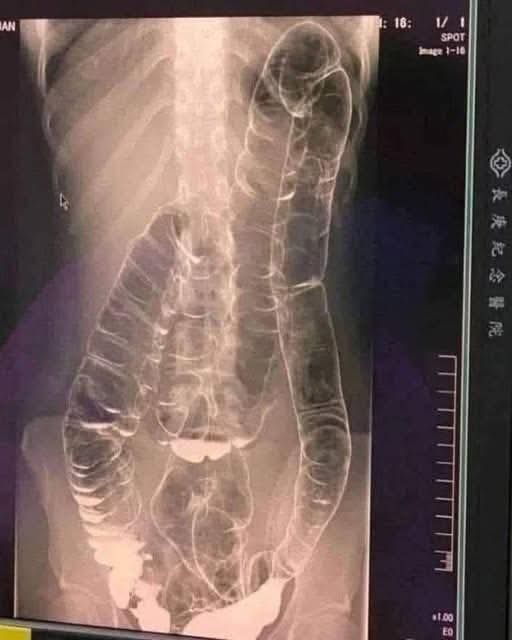

This is an X-ray image of a young woman who suffered from chronic constipation. One day, after experiencing continuous symptoms for over two weeks, she went for a medical check-up and received the X-ray results shown below…

A young woman suffering from years of chronic constipation experienced a severe decline in her condition when she went more than two weeks without a bowel movement. Concerned about her worsening symptoms, she finally sought medical attention, only to receive alarming news.

When waste accumulates in the colon due to an inefficient digestive system, it causes severe discomfort and bloating. Over time, the colon expands beyond its normal size, struggling to contain the excessive buildup of feces. In this case, medical imaging revealed a severely distended colon that had enlarged so much it reached up toward the chest, dangerously close to the heart. The stretching had nearly erased the colon’s natural folds and wrinkles, essential for its proper function. Left untreated, this condition could have led to life-threatening complications.